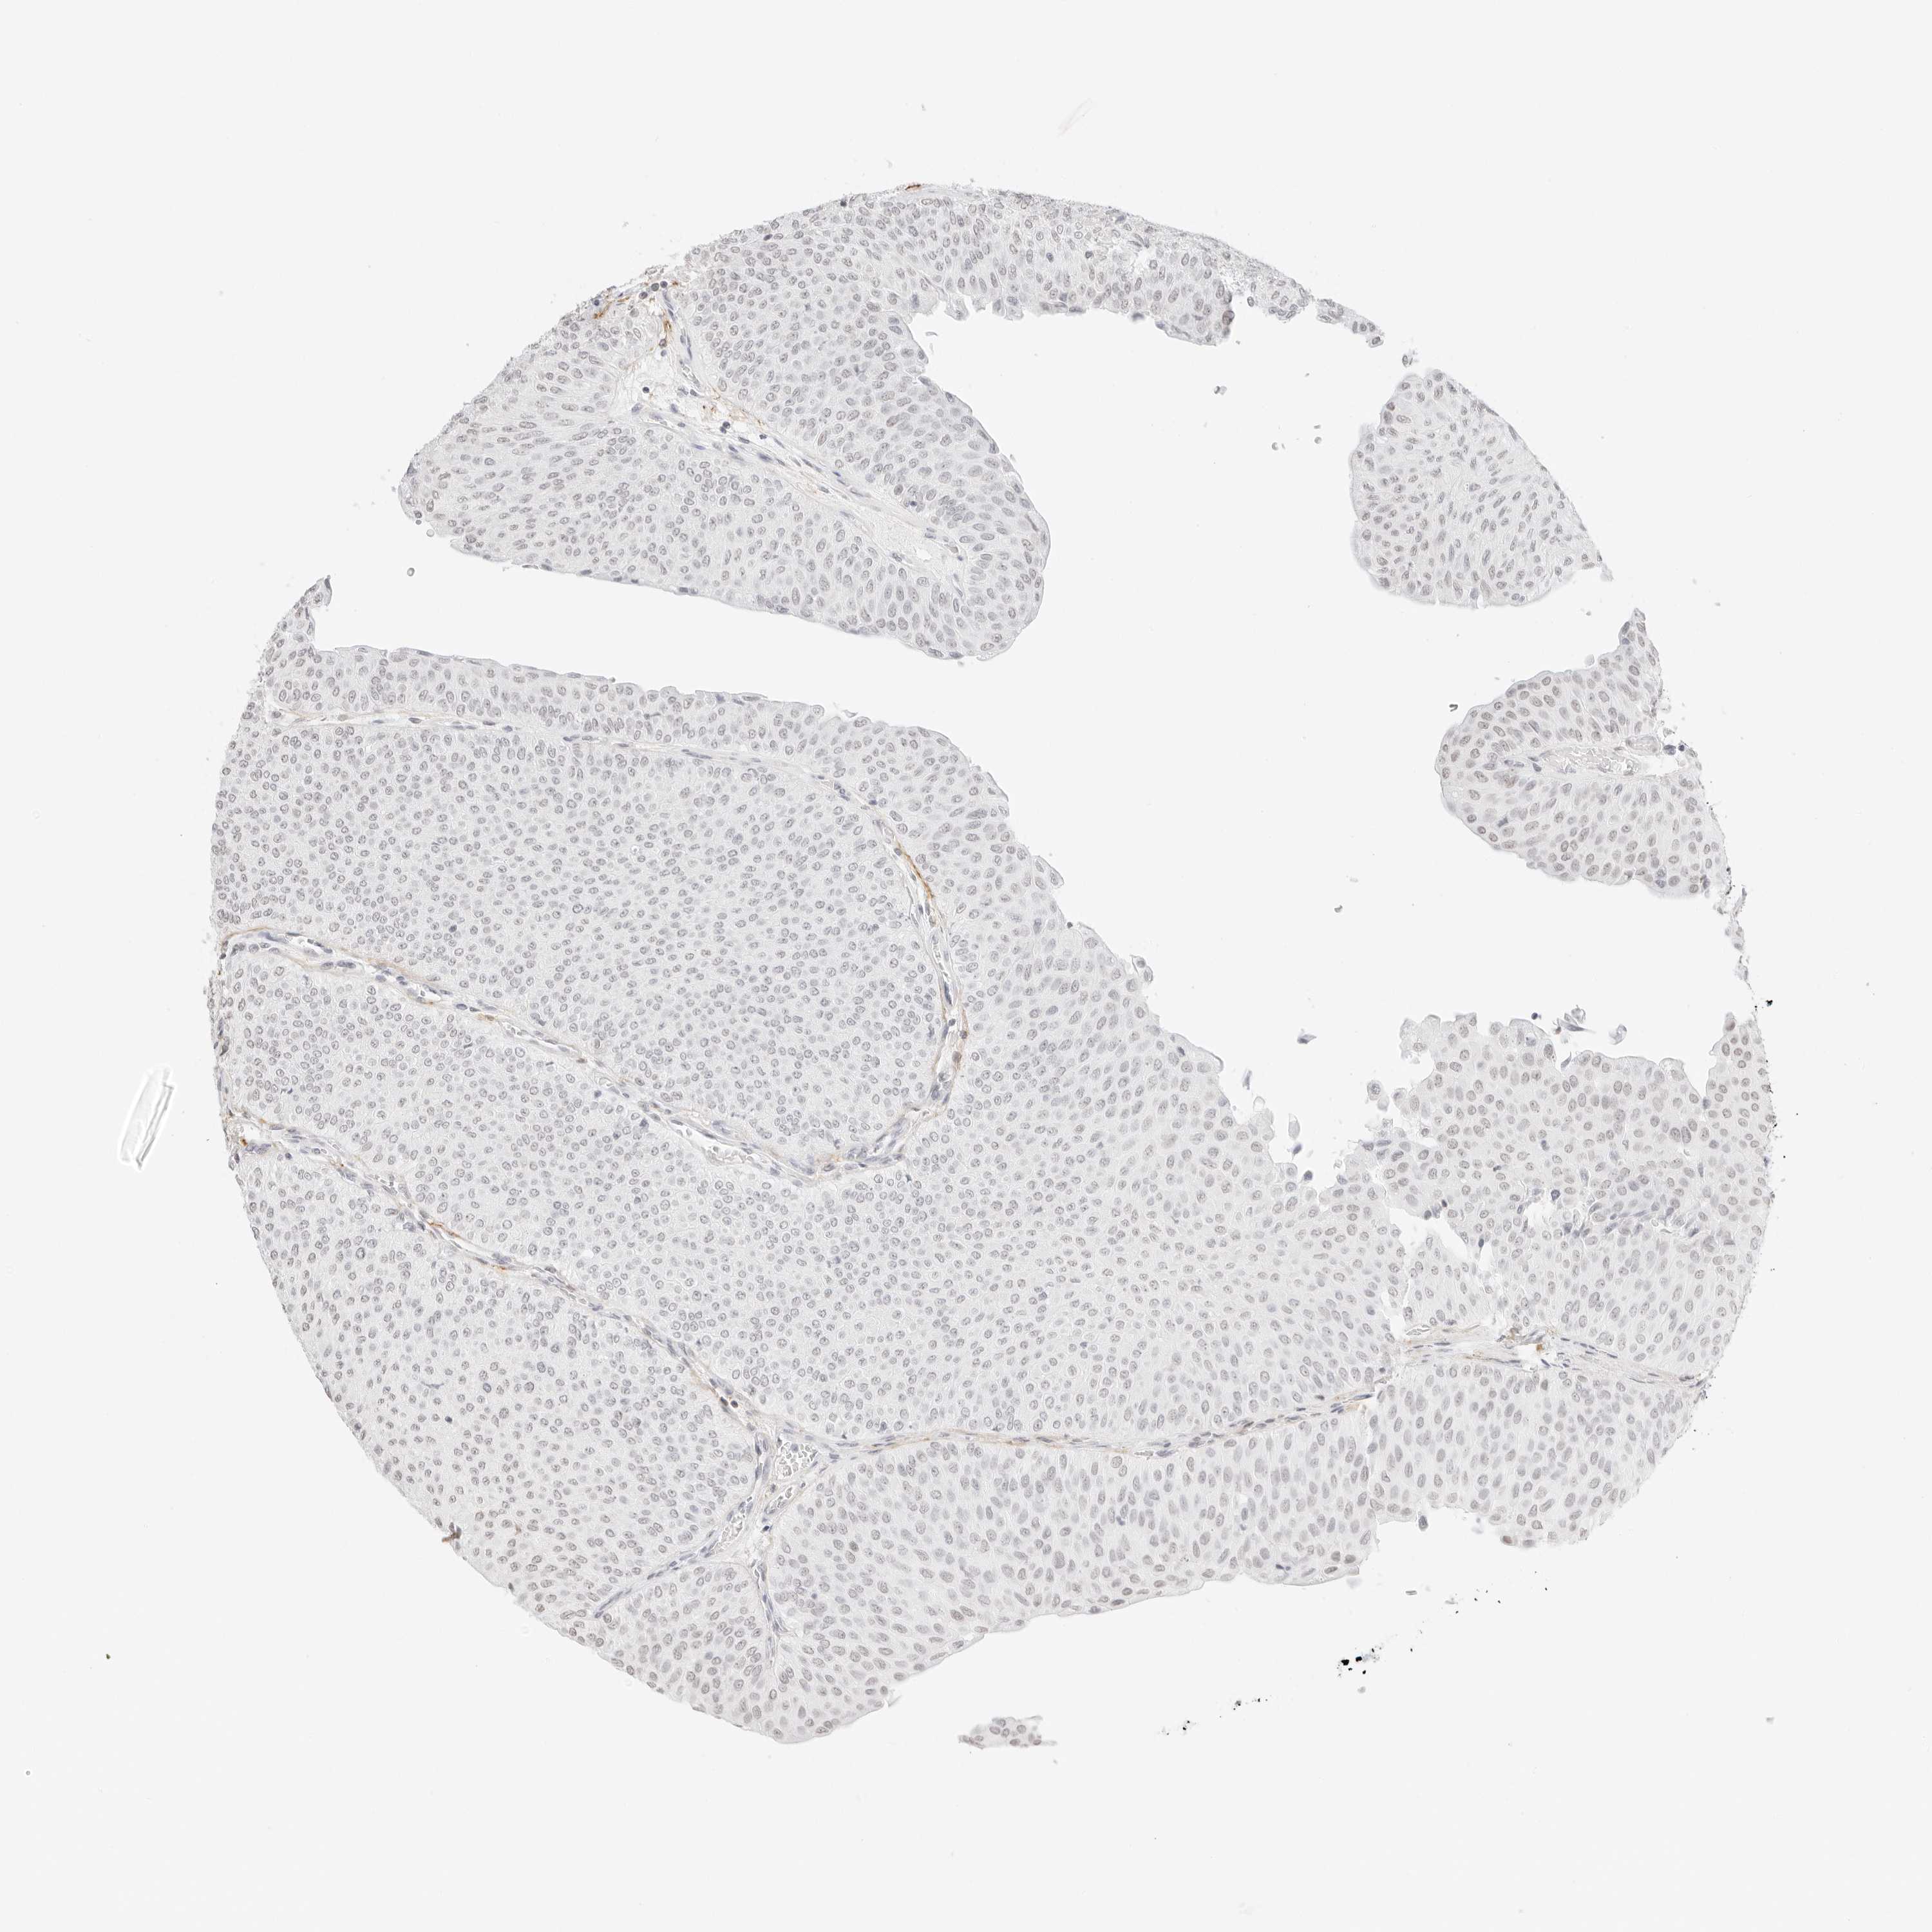

UROTHELIAL CANCER - Protein expressioni

A mouse-over function shows sample information and annotation data. Click on an image to view it in a full screen mode. Samples can be filtered based on level of antibody staining by selecting one or several of the following categories: high, medium, low and not detected. The assay and annotation is described here.

Note that samples used for immunohistochemistry by the Human Protein Atlas do not correspond to samples in the TCGA dataset.

Antibody stainingi

Antibody staining in the annotated cell types in the current human tissue is reported as not detected, low, medium, or high, based on conventional immunohistochemistry profiling in selected tissues. This score is based on the combination of the staining intensity and fraction of stained cells.

Each image is clickable and will lead to virtual microscopy that enables deeper exploration of all samples and also displays staining intensity scores, fraction scores and subcellular localization as well as patient and tissue information for each sample.

Antibody HPA000848

Antibody HPA000868

Antibody CAB025843

Staining

High

Medium

Low

Not detected

Intensity

Strong

Moderate

Weak

Negative

Quantity

>75%

75%-25%

<25%

None

Location

Nuclear

Cytoplasmic/membranous

Cytoplasmic/membranous,nuclear

Urothelial carcinoma, High grade

Urothelial carcinoma, Low grade